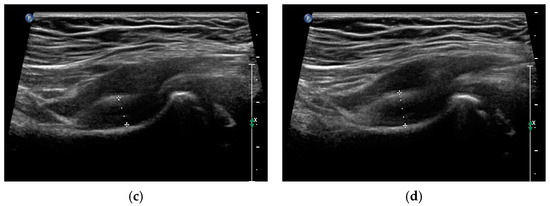

- Czyrny, Z. Osgood-Schlatter disease in ultrasound diagnostics—A pictorial essay. Med. Ultrason. 2010, 12, 323–335. [Google Scholar] [PubMed]

- Kaneuchi, Y.; Otoshi, K.; Hakozaki, M.; Sekiguchi, M.; Watanabe, K.; Igari, T.; Konno, S. Bony Maturity of the Tibial Tuberosity With Regard to Age and Sex and Its Relationship to Pathogenesis of Osgood-Schlatter Disease: An Ultrasonographic Study. Orthop. J. Sports Med. 2018, 6, 2325967117749184. [Google Scholar] [CrossRef] [PubMed]